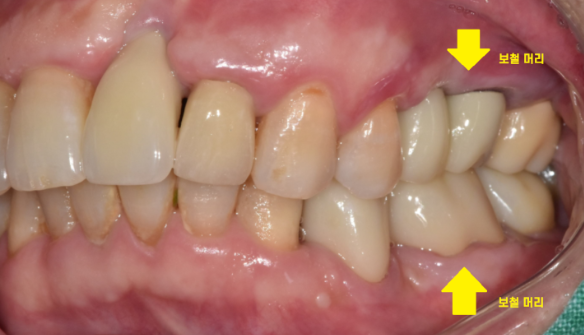

상일동역 치과 수술 직후의 사진입니다.

사진을 보시면 나사가 하나 들어간 것을

확인하실 수 있는데요.

환자분이 생각하시는 머리는 이런 형태이실겁니다.

무언가를 씹을 수 있는..